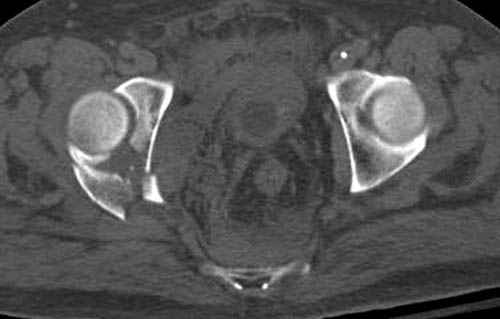

Дополнительно имеется перелом ацетабулума: задняя

колонна с полупоперечным переломом, и переломы костей лица.

На седьмой день зафиксирован перелом ацетабулума через задний доступ. Перед операцией для профилактики DVT, IVC фильтер, также получает Lovenox.

По снимку создается впечатление о высоком поперечном переломе, задней колонны, стенки; почему не пользовались *magic screw*?

По возможности вышлите снимки, сканы таза до

реконструкции, интраоперационные.

Не хотелось отклонятся от основной темы, поэтому здесь краткие ответы..

Латеральное положение облегчает проведение тракции через вертел, за 5 мм стержень за вертел (грузом через тракционное приспособление), на обычном рентгенопрозрачном операционном столе, а для положения на животе, наверное, Judet Table более приемлем, потому что там имеется латеральное тракционное устроиство.

Там множество обычных 2.7 мм шурупов, потом идет фиксация основными пластинами.